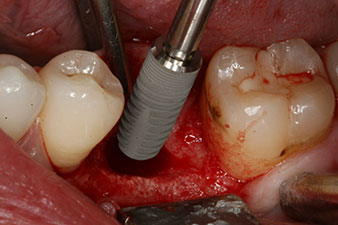

peri-implant bone deficit

Fig. 5: The peri-implant bone deficit must be compensated with autogenous bone chips to restore the peri-implant tissue contour.

These values could have indicated open healing or even immediate restoration. Due to the insufficient crestal bone volume at the implant, the region was augmented with the bone chips collected during preparation of the implant bed and sutured to exclude saliva.